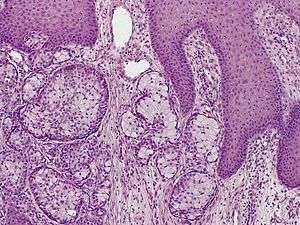

Eccrine carcinoma, alveolar type

Eccrine carcinoma (also known as a syringoid carcinoma) is a rare cutaneous condition characterized by a plaque or nodule on the scalp, trunk, or extremities.[1]:669